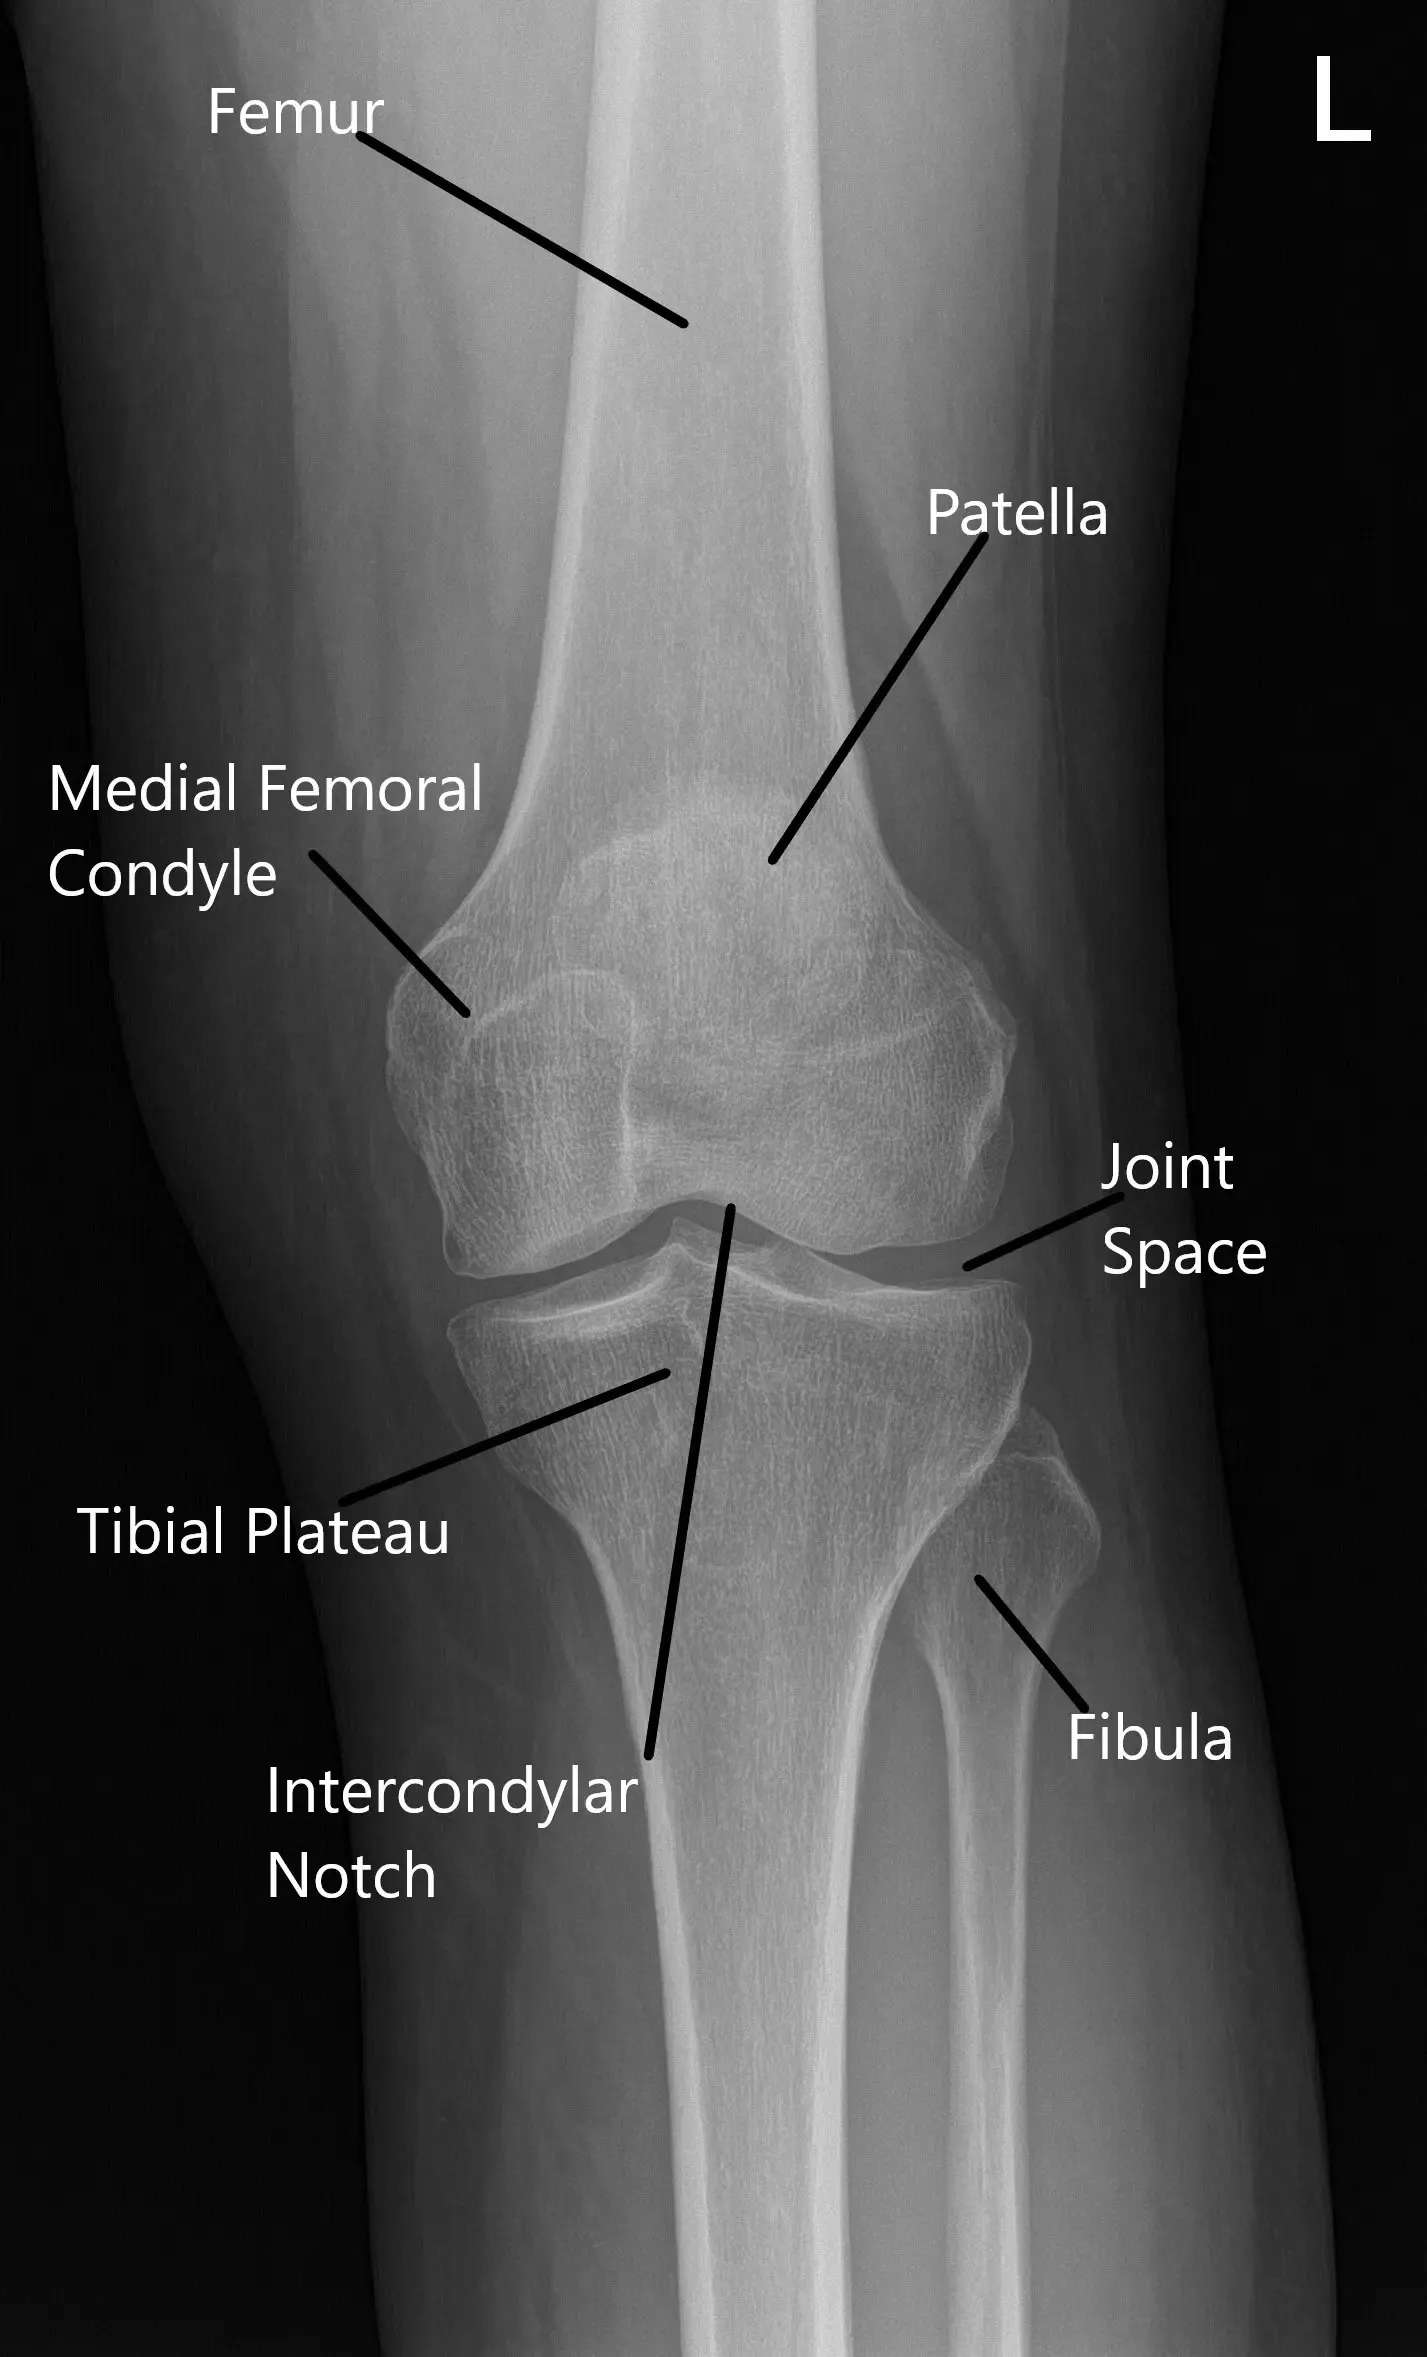

How the Body Part Normally Works? (Relevant Anatomy)

The patellofemoral joint is where the patella (kneecap) rests within the groove of the femur (thigh bone). The knee joint functions by allowing smooth bending and straightening movements, with the patella helping to stabilize and guide these motions. In PFPS, the alignment of the kneecap becomes compromised, often due to muscle imbalances, tight ligaments, or poor training, leading to pain and discomfort.

Normal X-ray of the knee joint showing the various structures in the Anteroposterior and Lateral view.